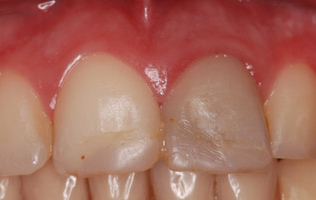

Cas 4 : Facette sur 1 incisive centrale Couronne + inlay-core céramisé sur l'incisive symétrique